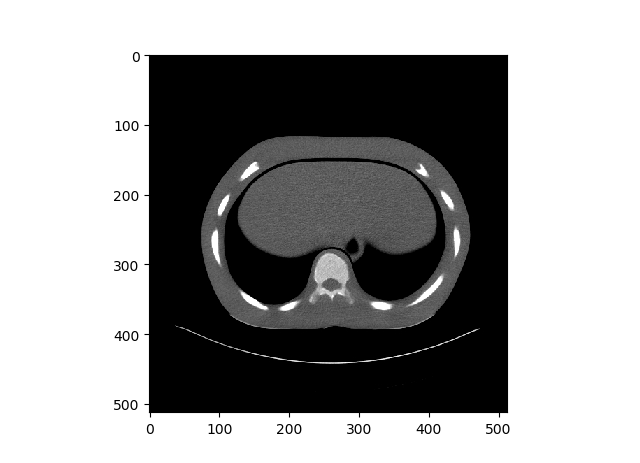

Case 1: Training and Results

Case 1 was normal stochastic gradient descent, as seen above, the overall shape of the CT Scan can be seen. However it is very hard to see. Right image is one of original image for comparison.

Case 2: Training and Results

For gradient noise, you can kinda? see something in the middle. However there is no way to tell that this was a Lung CT Scan image. Right image is one of original image for comparison.

Case 3: Training and Results

Now with Dilated Back Propagation, we can see that the resulted denoised images look very similar to the case 1 results. However, again very hard to tell exactly which is the lung part of the CT Scan. Right image is one of original image for comparison.

Case 4: Training and Results

Now we can clearly see what we are looking at. However it lacks details, and I mean A LOT of details. If you compare the GIF with the right image, you can barely make out the details. Right image is one of original image for comparison.